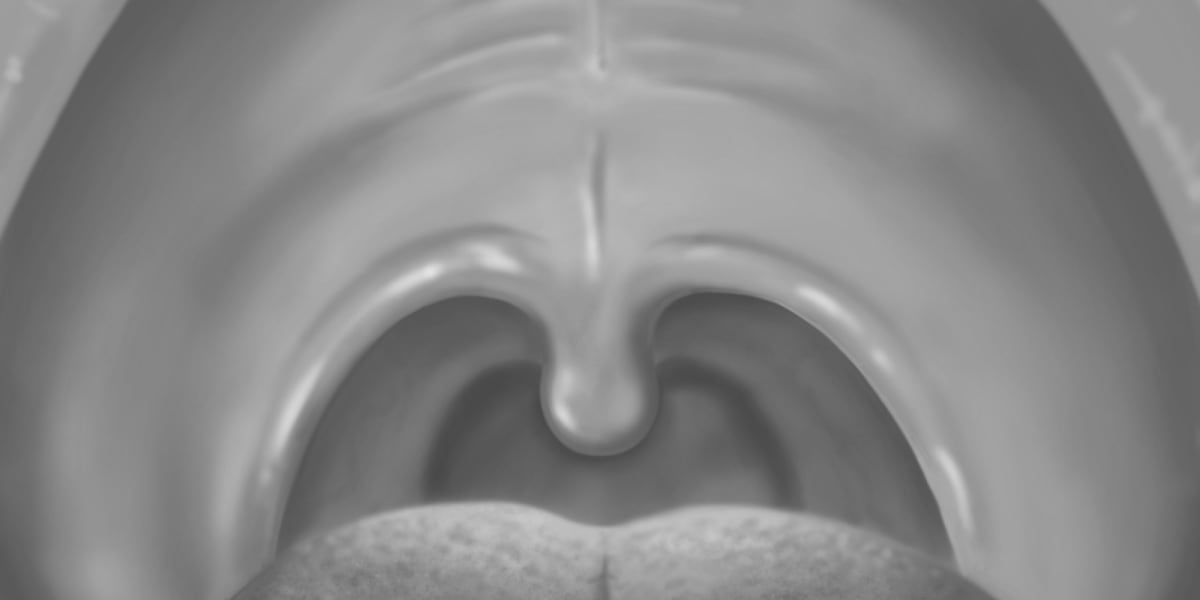

What Causes The Uvula To Elongate . Elongated uvula is relatively an uncommon condition. Experts still don’t fully understand all the reasons why people have uvulas. It’s the flesh that hangs in the back of your throat. It helps you swallow and speak. What does the uvula do? Upper airway obstruction is often a missed complication. an enlarged uvula is often caused by infection, an allergic reaction, or irritation from chemicals or medical. the uvula contacts the food passing through the mouth, that is, products that are hot and which can increase tissue.